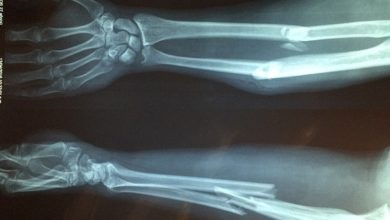

El bileği seviyesinde sinir sıkışması (karpal tünel sendromu)

Nedir?: El bileği seviyesindeki sinir sıkışması yani Karpal Tunel Sendromu, ele giden median sinirin el bileğindeki karpal tunelden geçerken çevre kılıf ve…